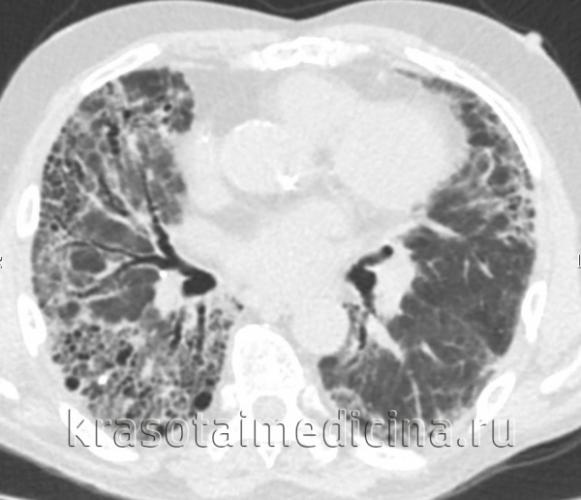

Рентгенологическая картина полиморфная, потому что показывает проявления не только самого пневмосклероза, но и сопутствующих болезней: эмфиземы легких, бронхоэктатической болезни, бронхита с хроническим течением и проч. Типичные петлистость, усиления и деформация легочного рисунка по ходу бронхиальных разветвлений, поскольку уплотняются бронхиальные стенки, имеют место склероз и инфильтрация перибронхиальной ткани.

Бронхография показывает девиацию или сближение бронхов, сужение и отсутствие мелких бронхов, деформацию стенок. Спирография является эффективным диагностическим методом при подозрении на пневмосклероз, выявляет уменьшение ЖЕЛ, ФЖЕЛ, индекса Тиффно.

Над пораженной зоной физикальные обследования обнаруживают ослабление дыхания, сухие или влажные хрипы, притупление перкуторного звука. Достоверным диагностическим методом является и исследование легких. Даже если симптомов нет, рентген помогает обнаружить изменения при их наличии, характер их, распространенность, то, насколько они выражены. Более точно оценить состояние нездоровых зон ткани легких могут магнитно-резонансная томография, бронхография, КТ легких.

Рентгенограмма показывает такие изменения пораженного легкого:

- уменьшение его в размерах

- усиление легочного рисунка по ходу разветвлений бронхов

- легочный рисунок сетчатый и петлистый по причине деформации стенок бронхов

- «сотовое легкое» в нижних отделах